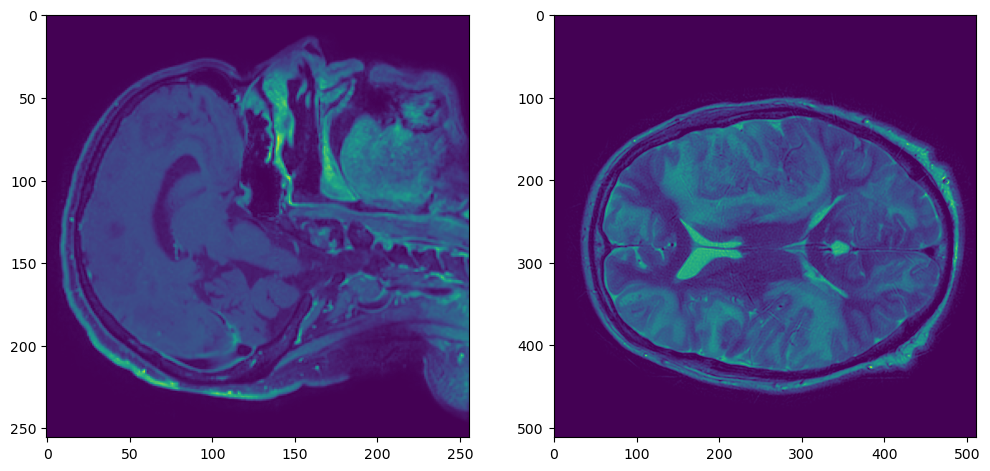

plt.figure(figsize=(12,6))

plt.subplot(121)

plt.imshow(t1_nib_array[:,:,t1_nib_array.shape[2]//2])

plt.subplot(122)

plt.imshow(t2_nib_array[:,:,t2_nib_array.shape[2]//2])

t1t2